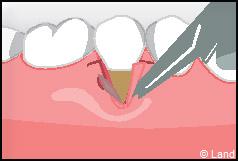

Les greffes de conjonctifs enfouis :

Destinées aux zones esthétiques, elles consistent à prélever la partie profonde du palais (site donneur).

Ce greffon est ensuite inséré sous la gencive au niveau de la récession (site receveur).